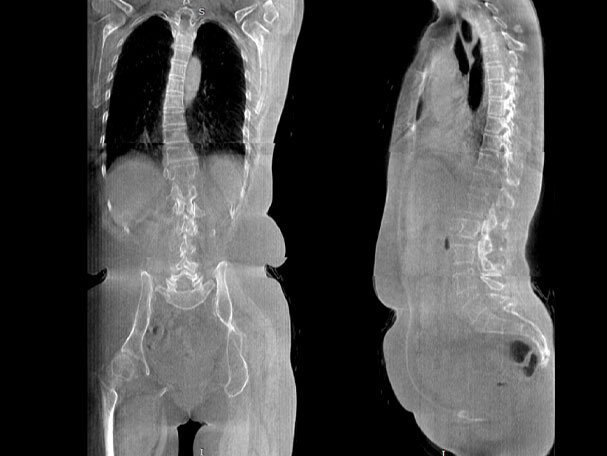

· 補位CT,提供負重位三維影像

· 引領普放走向三維精準診斷時代

填補常規CT/MR空白

VR體繪制重建

氣道三維影像重建